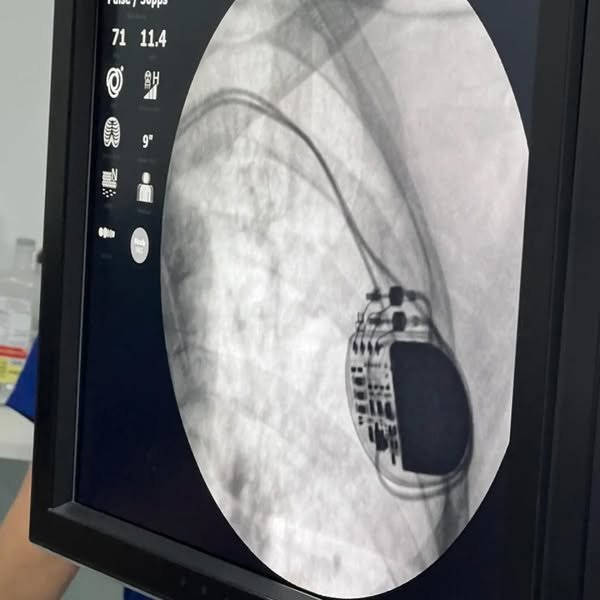

O marcapasso transcutaneo é um dispositivo médico usado para estimular o coração através da pele, com o objetivo de corrigir ritmos cardíacos lentos ou bloqueios cardíacos.

O paciente que recebeu o marcapasso estava internado na unidade de internação clínica do hospital e o procedimento foi um sucesso e totalmente pelo SUS.

É um fato inédito no Litoral Norte.

Este foi o primeiro paciente a ser atendido, entre muitos que aguardam a realização deste procedimento nas referências de alta complexidade em cardiologia em Porto Alegre.